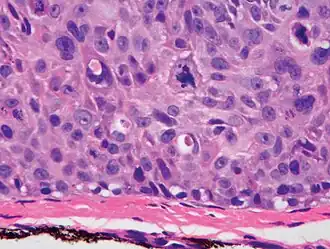

Degree of differentiation

Poorly differentiated, where attempts at keratinization are often no longer evident. This is a clear-cell squamous-cell carcinoma. The dysplastic cells infiltrated cords through the dermis. Poorly differentiated cSCC has greatly enlarged pleomorphic nuclei showing a high degree of atypia and frequent mitoses.[12] -

Poorly differentiated clear-cell squamous-cell carcinoma. For this type of cSCC, immunostains will likely be required to classify it unless other areas of the tumor show obvious squamous-cell features, such as seen here (arrow).